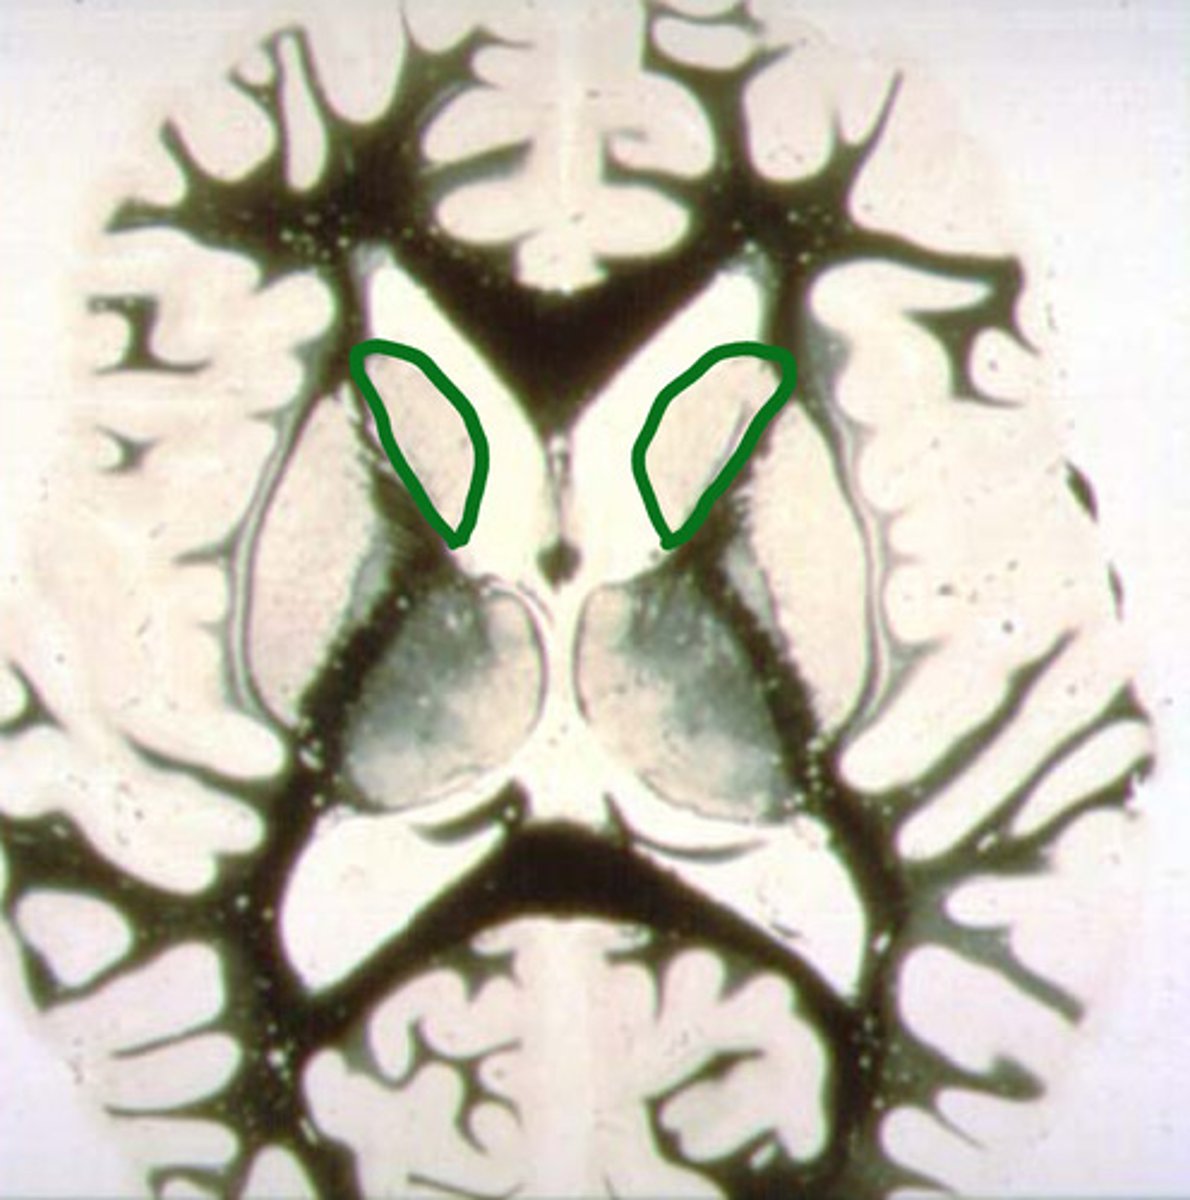

blue - thalamus

purple - hypothalamus

identify the structures

thalamus

identify the structure